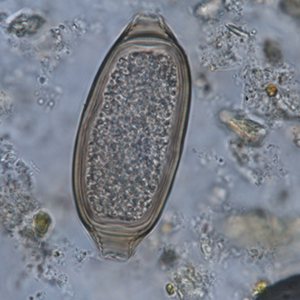

Les œufs de trichure sont ovales, symétriques, à paroi régulière, lisse et à bouchons polaires saillants. Ils ont une forme de tonneau et mesurent environ 50 à 80 µm de longueur pour 20 à 40 µm de largeur. Ils présentent, au site d’insertion de leurs bouchons polaires, des stries perpendiculaires à l’axe de l’œuf. Il est très difficile de distinguer les différentes espèces à l’examen coproscopique des œufs (Garcia, 2021).

- Les œufs de capillaire sont décrits comme ayant une forme de saucisse alors que ceux de trichure ont plutôt une forme de tonneau. Ce critère n’est pas forcément clairement visible

- Les œufs de capillaire ont des bouchons polaires en général plus aplatis que ceux de trichure mais lorsqu’ils sont légèrement dégradés certains œufs de trichure peuvent ne pas présenter de bouchon polaire proéminent.

- Les œufs de capillaire et trichures présentent des stries au niveau de leurs extrémités (à l’endroit d’insertion des bouchons polaires). Ces stries sont parallèles à l’axe de l’œuf chez les capillaires, et perpendiculaires chez les trichures. Cet élément est beaucoup plus visible et fiable que les deux précédents.

Les grains de pollen d’iris (Iris spp.) rentrent dans le diagnostic différentiel. Ces pollens présentent une même forme allongée et sont de dimensions semblables mais leur paroi est beaucoup plus fine et les extrémités moins marquées. Leur contenu est également beaucoup moins régulier (Petithory et al., 1995).